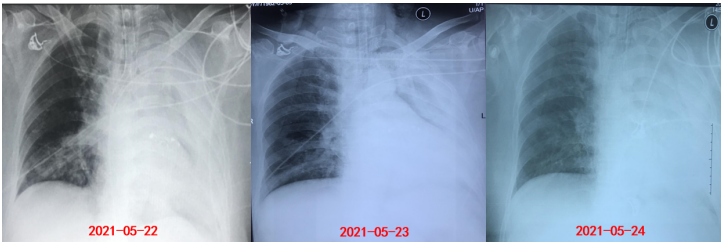

床旁胸片:左肺炎性病变;左下肺不张,左侧胸腔积液(图3)

图片

图3  患者入我科后床旁胸片

手术当天及术后2天床旁胸片如图4所示。术后第2天更换气管导管,右肺出现实变影。

图4  患者手术当天及术后胸片

经过多次气管镜清理,患者氧合指数稳步升高(表2)。6月1日(D13)撤机,予经鼻高流量氧疗。6月2日(D14)复查胸片提示左肺吸收较明显(图7)

图7  复查胸片